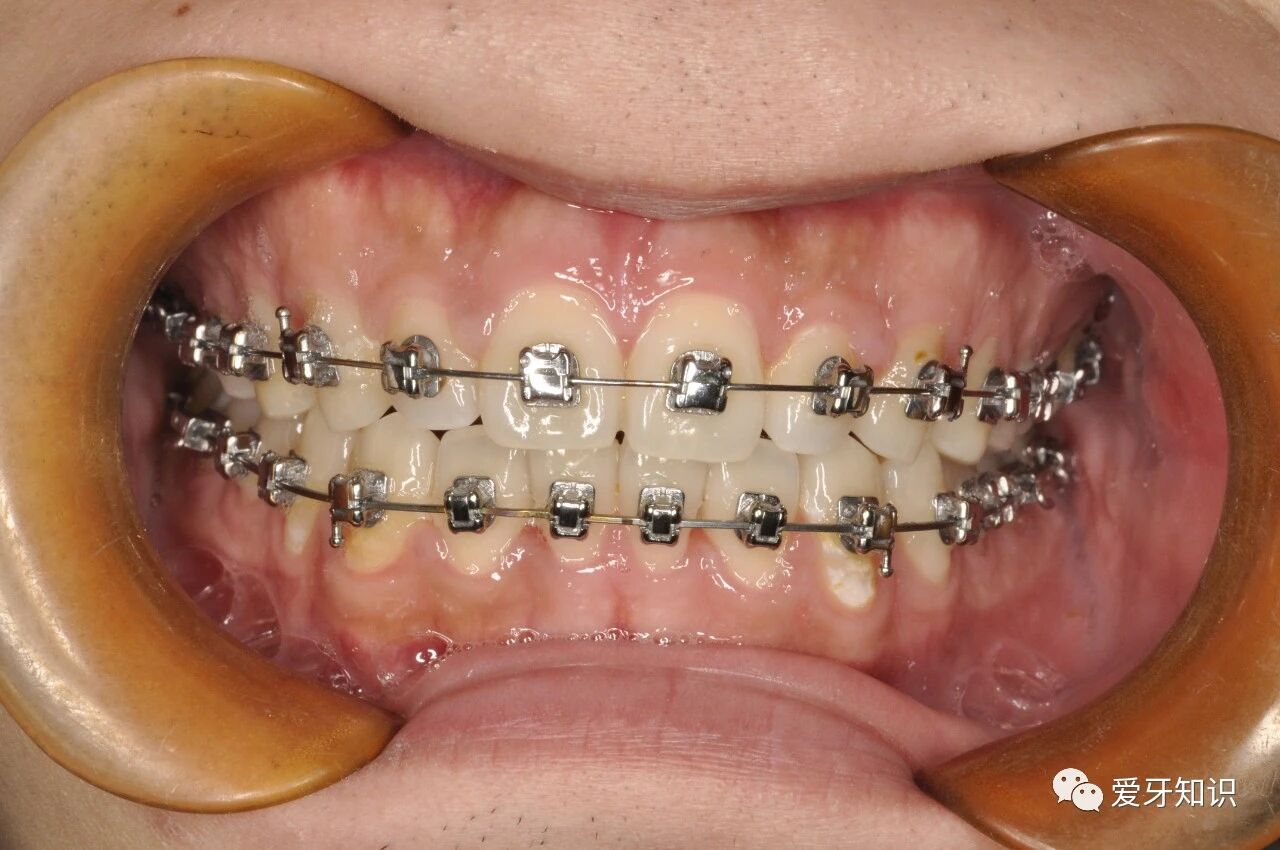

带牙套

分牙完成后就可以直接上牙套了。(戴牙套初期有点磨嘴,第一个星期可能会有牙周酸软感,之后不适症状将会消失。如果有口腔溃疡,可以晚上睡觉前喷桂林西瓜霜,补充点维生素B、锌等。)

一般是一个月复诊一次。具体时间医生会与你预约。(复诊一般情况就是给你加力,好让牙齿按照预期进行移动。)